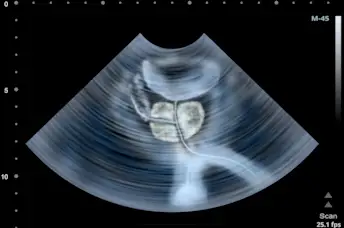

核磁共振扫描可以避免前列腺活组织检查

如果你的医生怀疑你患有前列腺癌,做核磁共振扫描可以避免前列腺活组织检查的医疗风险。